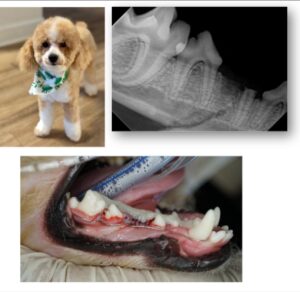

Veterinary examinations conducted in the days following the incident documented a fractured premolar and a right-sided mandibular fracture requiring multiple surgeries. Both the treating veterinarian and a veterinary dental surgeon specialist independently concluded Cosmos injuries were caused by significant blunt force trauma.